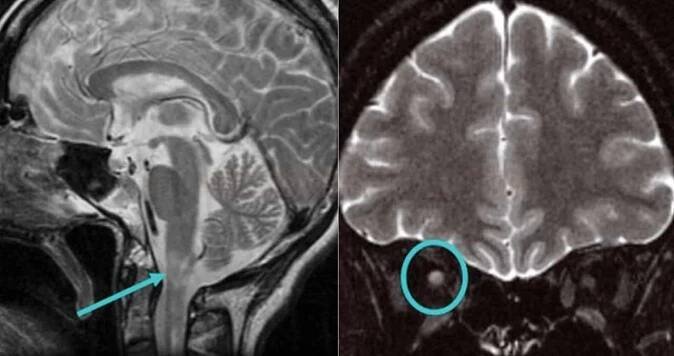

Mozkové metastázy – když nádor útočí na mozek od... | Léčba…

Mozkové metastázy je nádorové onemocnění, kdy nádor vznikne v jiné části těla a do mozku se následně rozšíří. Někdy se tento tumor nazývá sekundární. Jedná se…

…Mohou také růst v jiných částech hlavy a na mozek tlačit. „Jeden z prvních příznaků nemoci může být epileptický záchvat, dále například snížená pohyblivost končetin či ztráta řeči, bolest hlavy, závratě a zvracení. Proto je nutné nepodceňovat jakékoliv nestandardní změny v organismu,“ upozorňuje mluvčí VZP.